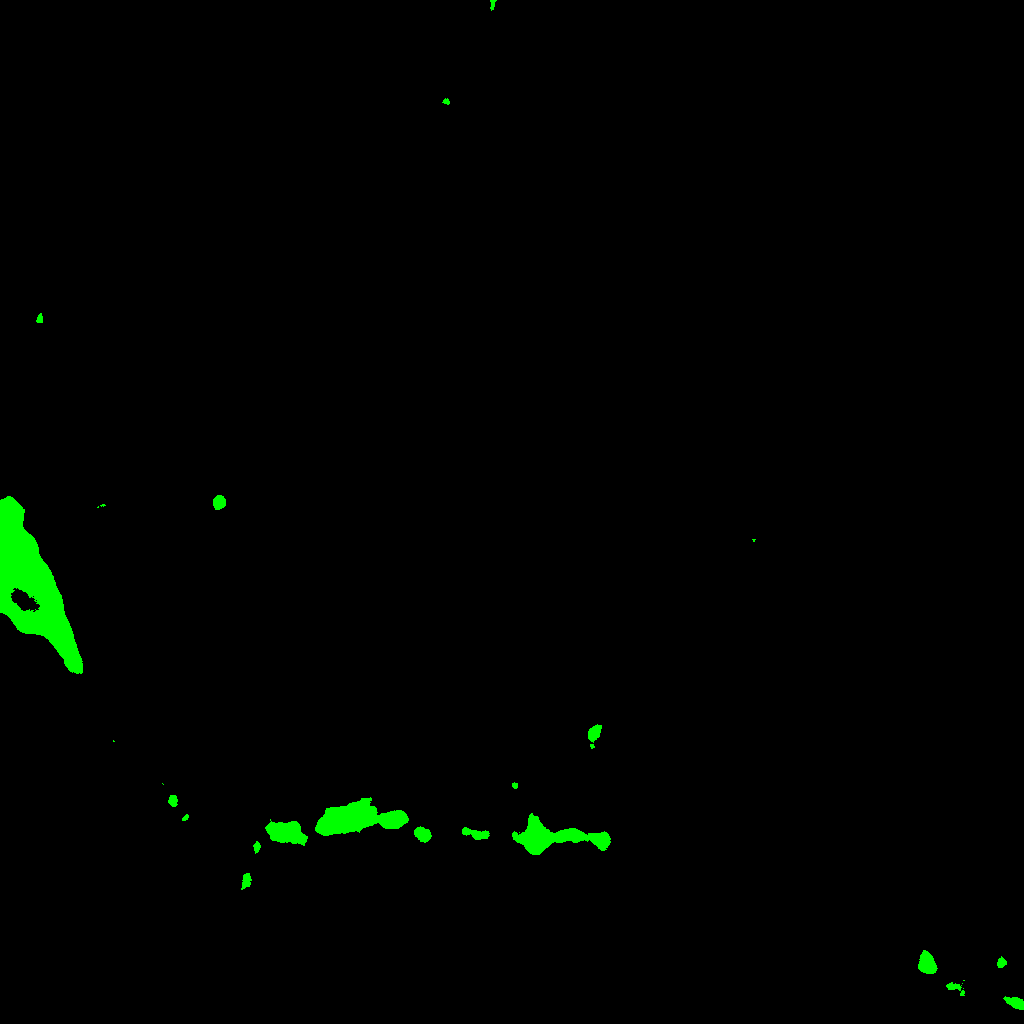

Let us analyze the information which can be extracted from such barcode. There are several connected components which live is reduced to the maximum projection image, the green connected components of Figure 5, and can be considered as noise. Notwithstanding that the components x1,x2subscript𝑥1subscript𝑥2x_{1},x_{2} and x3subscript𝑥3x_{3} (which are respectively the red, yellow and orange connected components of Figure 5) live a bit longer than green components; they are also short-lived; so, they cannot be part of the main structure of the neuron, it is likely that these components come from other biological elements. Eventually, we have the x0subscript𝑥0x_{0} component, the blue connected component of Figure 5, which lives from the beginning to the end of the filtration; therefore, as it lives from the beginning to the end of the filtration, it represents the structure of the neuron.

Refer to caption

Figure 5: Summary picture of the connected components from Figure 1 projection. Color code: green, components that last one plane. Orange, 2 planes. Yellow, three planes. Red, four planes and blue, components that are present in the eight planes.